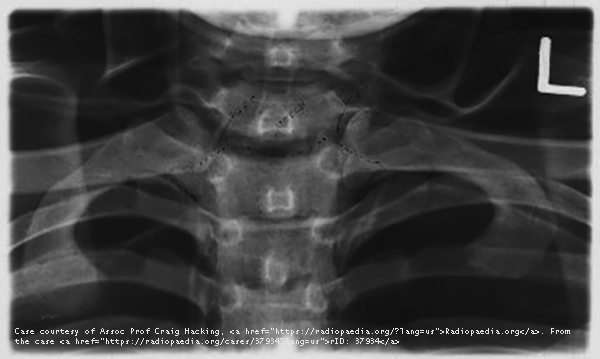

What structures are best demonstrated in the PA SC joint projection?

Lateral manubrium and medial ends of clavicles.

How do you position a patient for PA SC joints?

PA erect or recumbent, arms at sides/overhead, no rotation or tilt, CR perpendicular at T3.

What indicates correct positioning on PA SC joints?

Equal distance of SC joints from vertebral column.